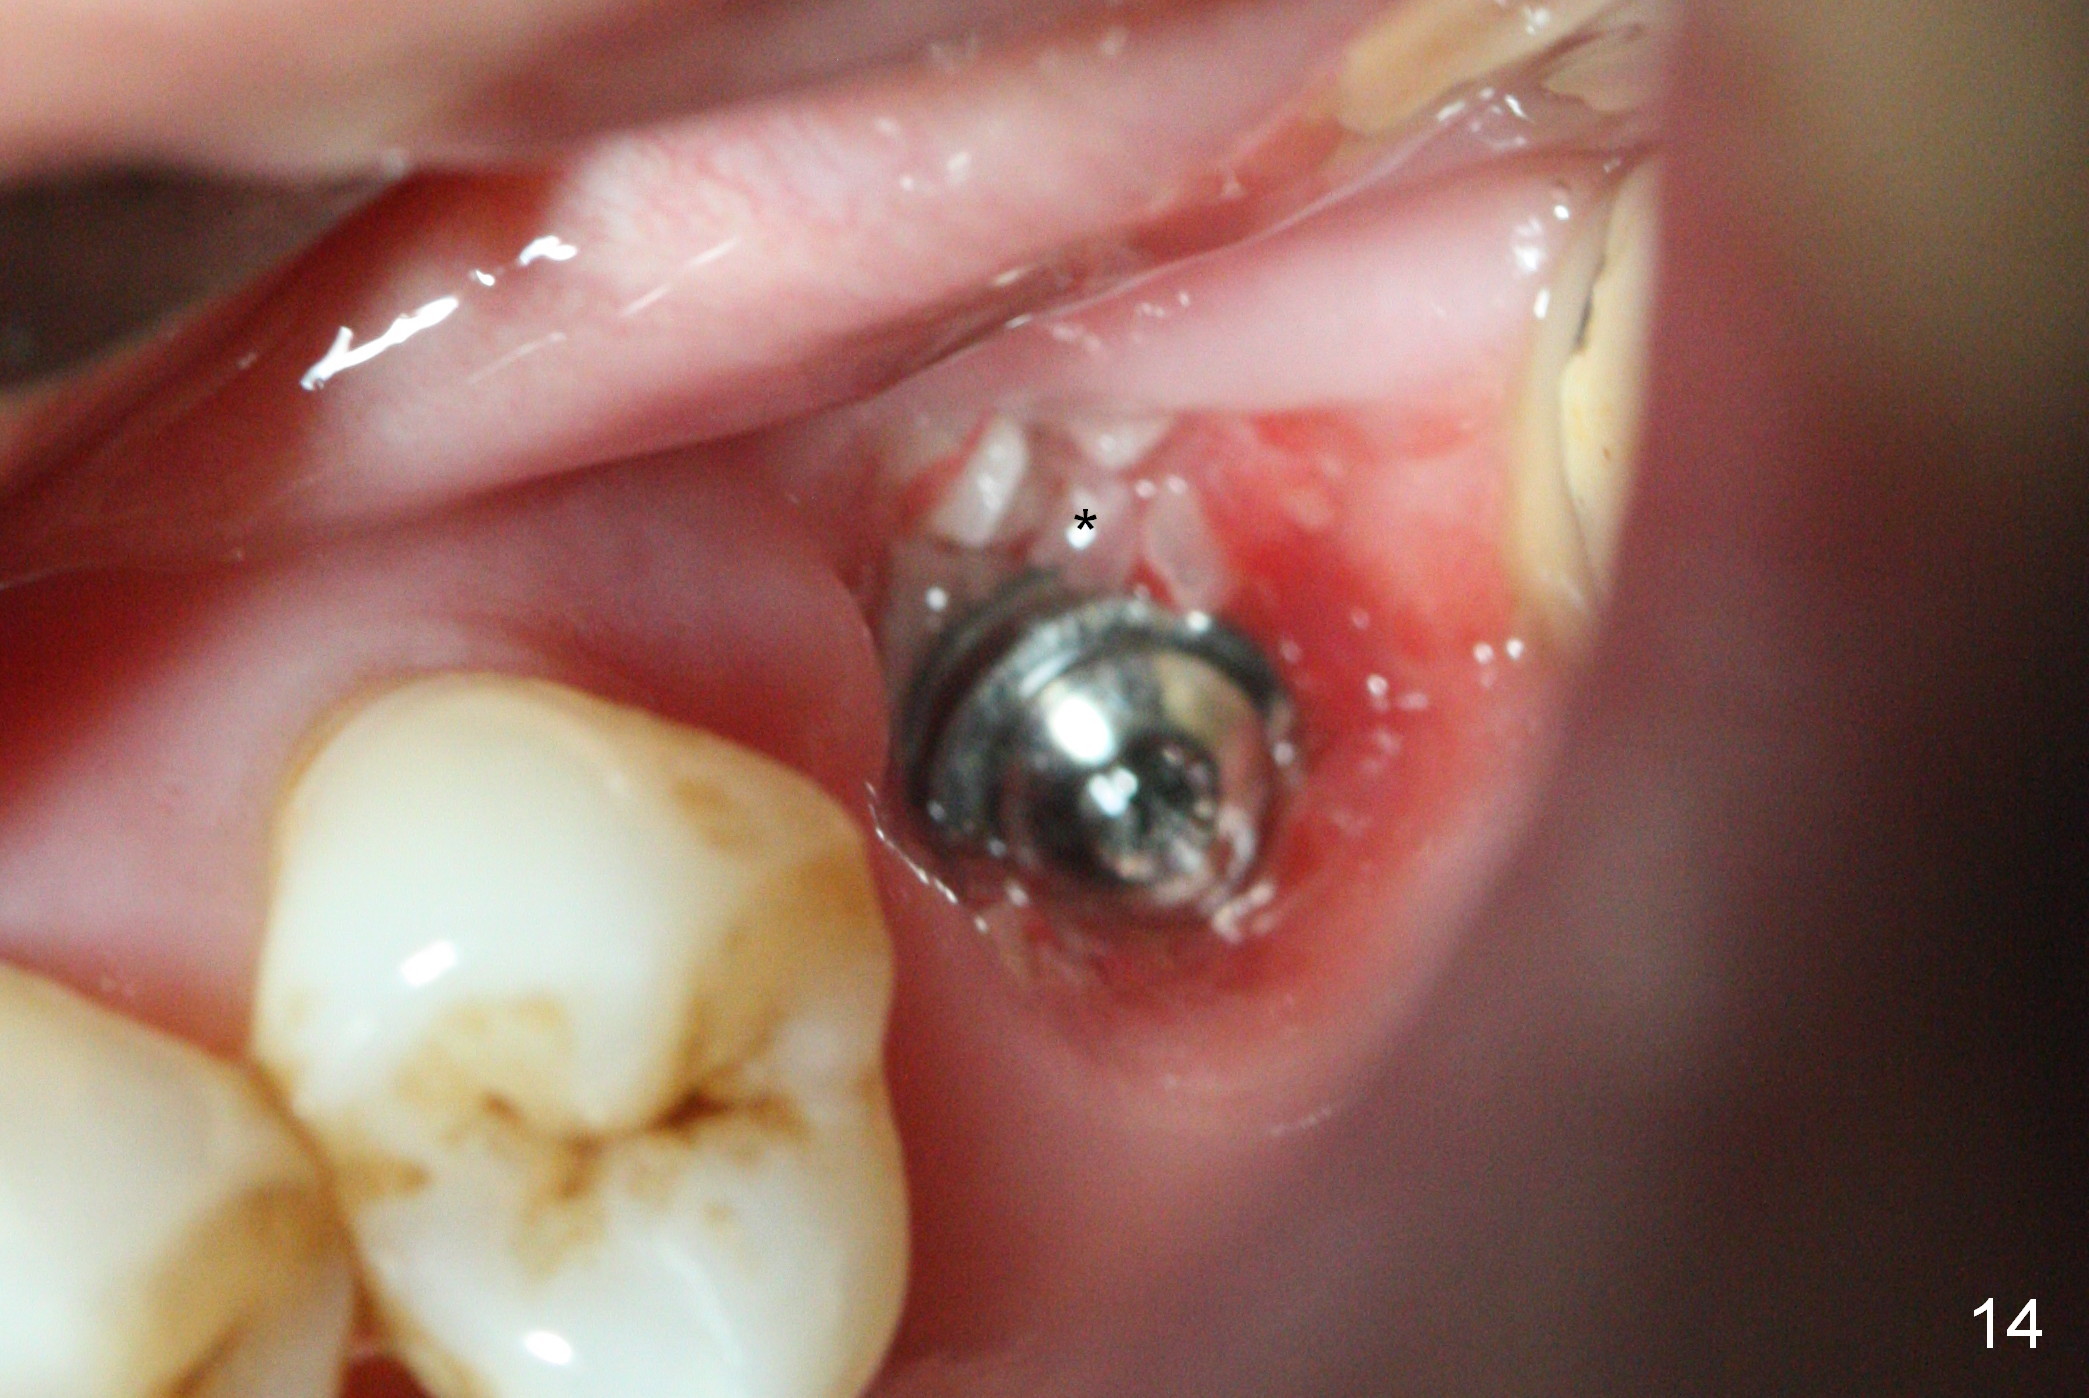

There is abundant subgingival calculus on the surfaces of the extracted tooth at #14 (Fig.1: P: palatal; MB: mesiobuccal), corresponding to the large empty socket (Fig.2 without septal bone, the buccal plate being low). Osteotomy is established palatally with Magic Expander (ME) 3.0 mm for ~ 3 mm deep (Fig.3,4) with minimal stability so that it moves during X-ray taking (Fig.4). Since the bone is dense, Magic drill 4.3 mm is used after application of ME 3.8 and 4.3 mm to complete sinus lift (Fig.5 (panoramic X-ray)). A 5x11 mm implant is placed with ~ 30 Ncm, followed by insertion of 6.5x4(3) mm Hexa abutment, bone graft and collagen membrane (Fig.6). The latter is kept in placed with an immediate provisional with clearance from the opposing dentition (Fig.7 *). Between the 1st and 3rd weeks postop, the buccal gingiva recedes with loss of bone graft (Fig.8 <) and implant thread exposure (Fig.9 * (A: abutment)). After inducing hemorrhage, allograft is placed (Fig.10 >), followed by collagen dressing (Fig.11 >). The wound closes by adding new acrylic (Fig.12 *). Thirteen days later, food is trapped in the buccal gap (Fig.13 ^). It appears that the provisional does not help wound healing. The provisional and abutment are removed; incorporating bone graft (Fig.14 *) and the implant are exposed. After placing collagen plug against the bone graft and implant, the wound is closed by periodontal dressing.